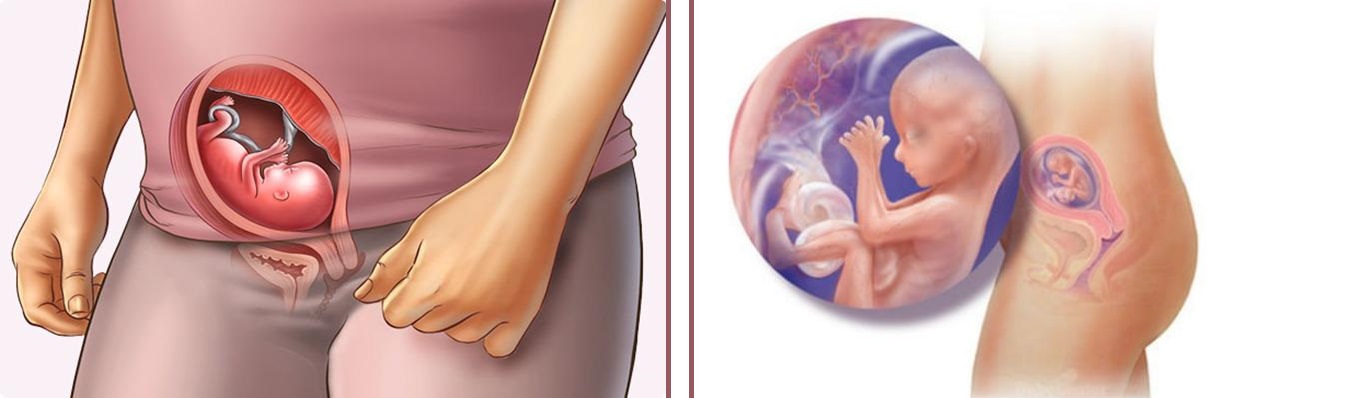

Расположение плода на 15-й неделе беременности: фотографии и иллюстрации